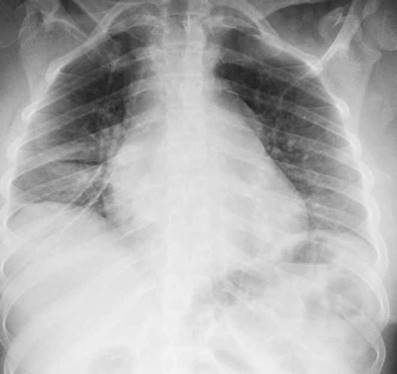

En los paraclínicos, como únicos hallazgos relevantes se encuentra un ensanchamiento del mediastino observado en rayos X de tórax (fig. 2), secundario a múltiples adenopatías de localizaciones paratraqueales, hiliares derechas, paraesofágicas y en estación 6, descritas en tomografía de tórax (fig. 3), e hipercalciuria correspondiente a un valor de 416 mg en 24 h. Se descartan otros procesos autoinmunes con negatividad para anticuerpos anticardiolipina IgG e IgM, anticuerpos antinucleares (ANA), anticuerpos extraíbles del núcleo (ENA), anticuerpos anticitoplasma de neutrófilos (ANCA) tinción perinuclear y citoplasmática, anticuerpos antiácido desoxirribonucleico (anti-ADN) nativo, y factor reumatoide. Se excluyen también enfermedades infecciosas como virus de la inmunodeficiencia humana (VIH), sífilis y virus de las hepatitis B y C (tabla 1).